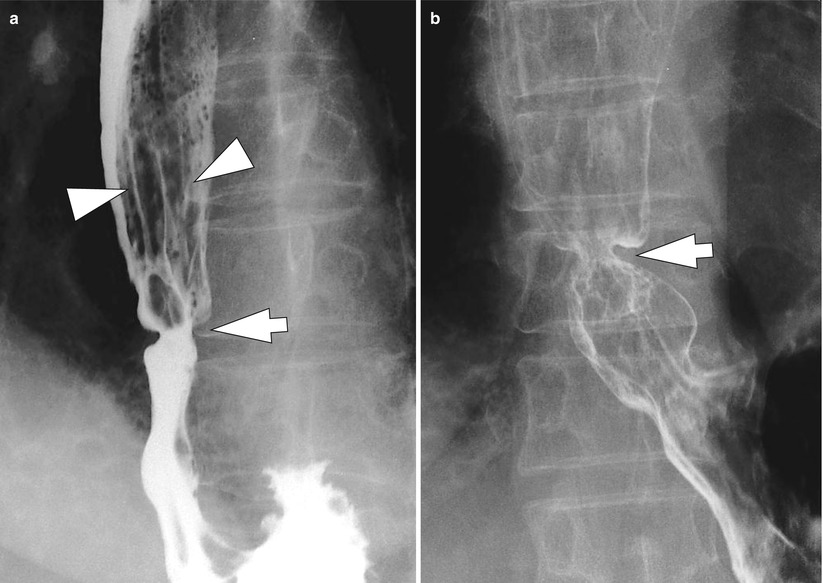

From radiologykey.com

Esophagitis Radiology Key Endoscopic Findings Of Reflux Esophagitis gastroesophageal reflux disease (gerd) is notable for its high prevalence, variety of clinical. reflux esophagitis occurs in patients with gerd when toxic substances such as gastric acid, pepsin, and bile salts come into contact. the presence of endoscopic and/or histopathologic damage to the esophagus is called reflux esophagitis. incompetence of the lower esophageal sphincter allows reflux. Endoscopic Findings Of Reflux Esophagitis.